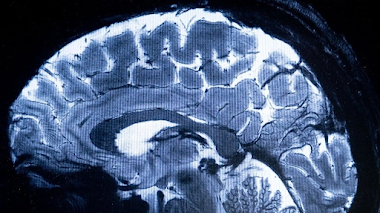

PRIMERAS IMÁGENES DEL ESCÁNER DE RESONANCIA MAGNÉTICA MÁS POTENTE DEL MUNDO

Escáner de resonancia magnética más potente del mundo muestra primeras imágenes del cerebro humano …